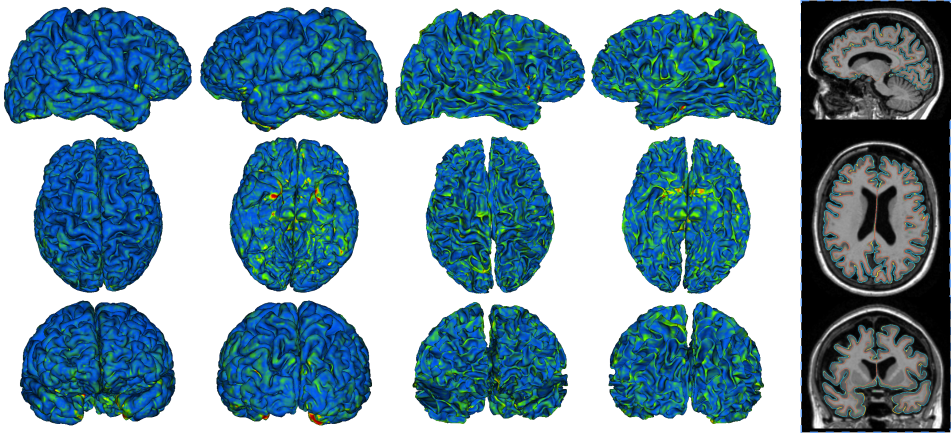

We now perform experiments with variations of the proposed DeepCSR to measure the importance of its main components. The quantitative results are presented in Table 1, while the qualitative results are shown in Figure 4. See below a brief summary of the dataset and evaluation metrics used, in addition to the detailed description of these experiments and the discussion of their results.

Hypercolumn features. It is the most important component in our model, since we are not able to recover the high frequency details in the cortical surfaces without it. In order to support this claim, we remove the hypercolumn formation steps from our encoder depicted in Figure 2, reshape the encoder’s last layer to output a 512-dimensional vector, use this vector as the decoder input, and train this model as before. These changes remove the hypercolumn schema but keeps the model with similar capacity since no layer or weights are removed. The performance of such a model is reported in the fourth row of Table 1 and it is much worse than the proposed model for all the evaluation metrics. Furthermore, Figure 4 depicts oversmoothed cortical surfaces that were reconstructed without hypercolumn features.

Output Resolution. We reconstruct cortical surfaces at different resolutions by predicting implicit surface representations for 3D evenly spaced grids of points of different sizes as explained in Section 3.3. Figure 4 depicts cortical surfaces generated at , , , and 3D evenly spaced grids of points. As the resolution grows, our method reconstructs more details of the cortical surfaces. The quantitative results are presented in the last three rows of Table 1.

We now compare the precision, accuracy, and runtime of the proposed model to the FreeSurfer V6 (cross-sectional pipeline) and FastSurfer. More specifically, we use the DeepCSR (SDF) trained on the ADNI dataset and reconstruct surfaces at resolution as explained Section 3.3. Table 2 summarizes the results and Figure 5 shows examples of reconstructed surfaces.